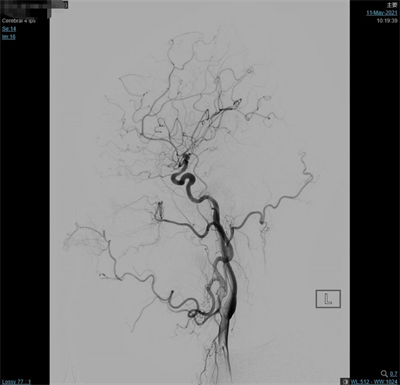

夹闭后造影